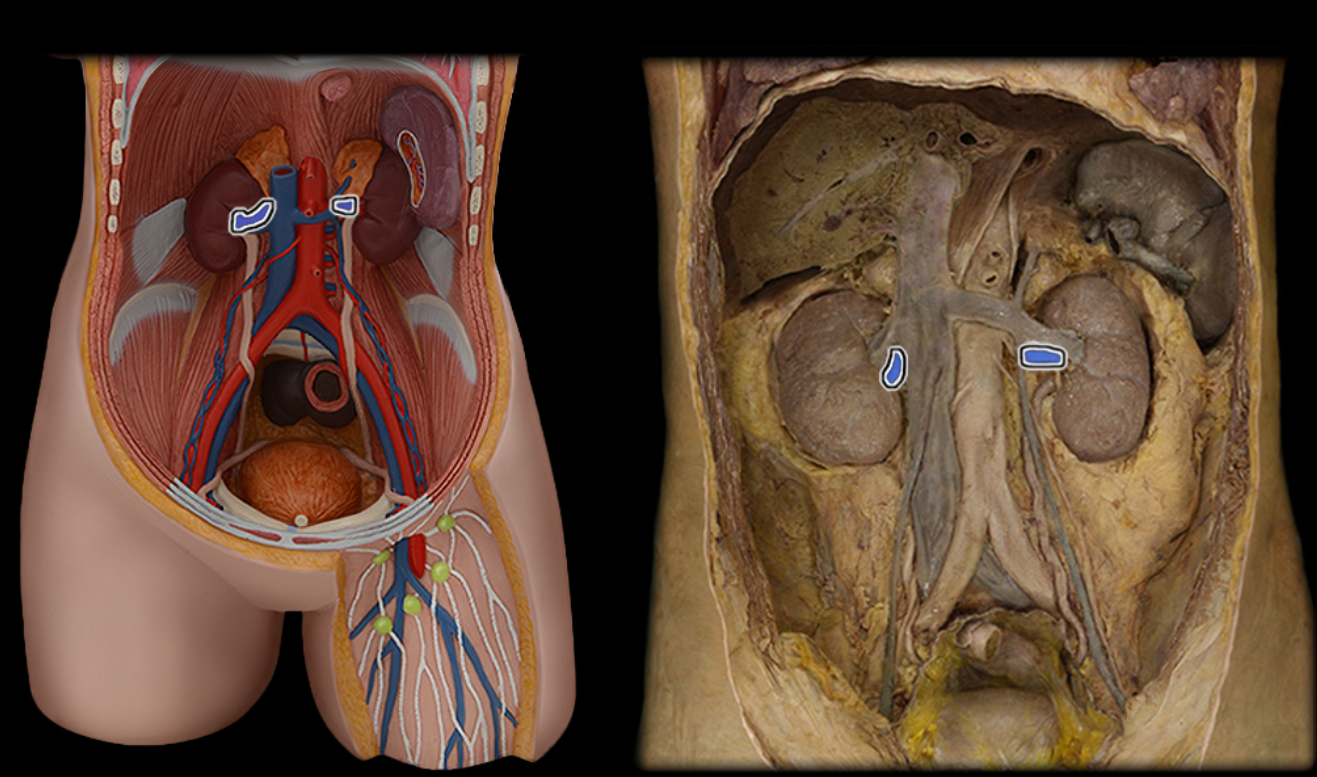

Abdominal aorta

Common iliac a.

Common iliac v.

External iliac a.

External iliac v.

Femoral a.

Femoral v.

Gonadal a.

Gonadal v.

Inferior vena cava

Lumbar a.

Lumbar v.

Renal a.

Renal v.

Superior mesenteric a.